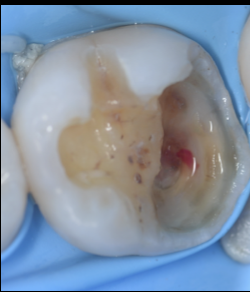

【池袋|歯髄温存療法(VPT)】神経を残す最先端の...